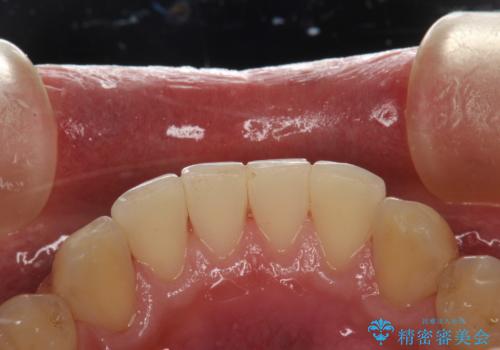

60分のPMTCで歯の黄ばみをきれいに除去

- 年末年始と忙しく、なかなか歯のケアがしっかりできなかった事と着色も気になるとのことで来院されました。PMTC60分コースを行いました。